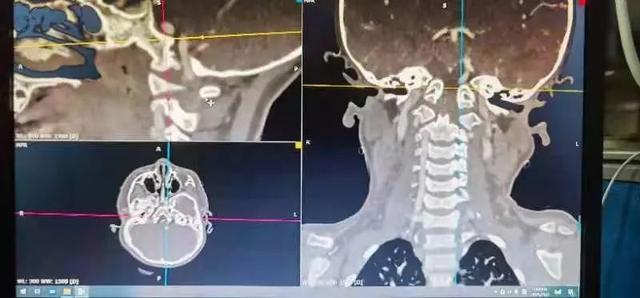

al-align:top;”> 孩子,望你早日康复! 这是一个关于 2岁宝贝的故事 为何这个幼儿平地摔倒,外表毫无受伤痕迹,却出现全身瘫痪,甚至呼吸功能衰竭? …… 为何凌晨时分,重医一院急诊科传来了救护车急促的汽笛声? …… 病史 患儿女,2岁零11个月; 于家中玩耍时平地跌倒致短暂意识丧失,苏醒后四肢瘫痪,自主呼吸微弱,病情危急! 为什么? 影像 患儿在当地医院作了急诊CT检查,发现…… CT显示:寰枢关节不稳 MRI:患儿呼吸不好,病情已不允许作了 分析 1. 尽管没有MRI检查,但根据CT显示的寰枢椎不稳,结合患儿四肢瘫痪,自主呼吸微弱的症状,颈延髓损伤明确; 2. 临床诊断:1)寰枢椎脱位 2)颈延髓损伤 怎么办? 方案 刻不容缓,做急诊手术准备! 寰枢关节不稳必须立即解决,否则有延髓再损伤的风险! 急诊手术:“寰枢椎复位+颈1-2融合内固定术+后路寰枕减压” 难点 患儿年龄小且发育较差,身高较同龄幼儿少10cm,体重仅仅11kg,上颈椎手术本就属脊柱高危手术之一,而幼儿的上颈椎骨质细小,在幼儿的上颈椎进行内固定手术,更是难上加难; 经验 重庆医科大学附属第一医院虽然是一所主要面向成人的综合性医院,但本院神经外科脊柱亚专业组,在幼儿脊柱手术方面具有丰富经验,尤其是对幼儿上颈椎损伤、颅底凹陷、先天性颅颈畸形、寰枢椎脱位等疾病,手术技术娴熟,成功完成过从2岁至13岁不同年龄幼儿的上颈椎手术。 既往病例文章分享: # 从13岁到2岁 # 一例“复杂”幼儿颅颈畸形 # 挑战幼儿 —— 3岁11月颅颈畸形手术病例分享 # 病例分享 || 幼儿复杂颅颈畸形 ……………… 本例患儿的手术在入院后2小时立即进行,并成功完成。解决了患儿寰枢椎不稳的风险,为其后续治疗的安全性提供了强有力的保障。 术后情况 术后CT示寰枢椎完美复位,寰枕区减压充分, 避免了患儿颈延髓神经功能二次损伤可能,为康复争取时间! 小宝贝术后虽然颈椎稳定了, 也减压了。 但是一时还无法脱离呼吸机, 也无法离开监护室, 无法见到自己爸爸妈妈! 不要害怕,宝贝! 重医一院神经外科脊柱亚专业组 和神经重症亚专业组的叔叔阿姨们 以及神经外科的护士小姐姐们, 会一直守护在你身边, 为你保驾护航! 宝贝加油! 相信你一定能战胜病魔,茁壮成长! 老晏说 幼儿脊柱疾病,亦在重庆医科大学附一院神经外科!